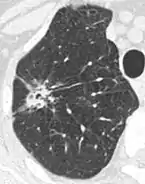

Calcifications and popcorn-like appearance, conferring a diagnosis of hamartoma.[9]

• In case of calcifications, a popcorn-like appearance indicates a hamartoma, which is benign.[3]